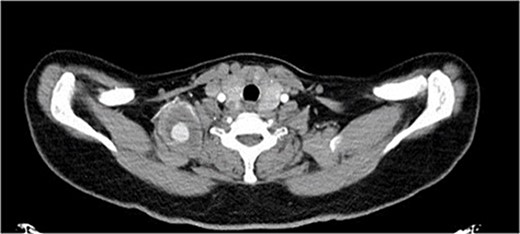

A 40-year-old female, who is a known case of type 1 diabetes mellitus, and hypothyroidism, on insulin and levothyroxine, was referred to our institute 4 months ago following trauma to her right shoulder from a falling drawer: complaining of swelling and pain around the right shoulder, palpable right distal pulses, and no discoloration or skin changes. Computed tomography angiography (CTA) showed partially thrombosed pseudoaneurysm at the right subclavian artery measuring 4.5 × 4 × 3.1 cm, most likely at the level of the costocervical trunk, specifically the highest intercostal artery (Figs 1 and 2). The subclavian artery and its branches were patent.

CTA, sagittal view showing the left supraclavicular pseudoaneurysm 4 × 3 cm.